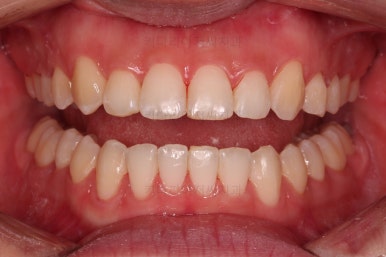

오늘 부산교정 키다리아저씨치과에 소개해 드릴 환자분은 앞니가 삐뚤고 덧니가 있어서 교정치료를 하고 싶어하셨던 분입니다.

초진 시 입안의 모습이에요.

입을 다물고 있을 때는 자연스러운 다물림이나 옆라인 등 모두 양호해요.

입을 벌리거나 말할 때는 앞니가 삐뚤고 덧니가 있어 미적으로 좋지 못하네요.

위아랫니가 모두 삐뚤어요.

특히 앞니가 삐뚤고 위아래 앞니가 고르게 덮여있는게 아니라 뒤죽박죽 엉켜있어서 치아의 마모도 굉장히 많이 되어있는 상태였어요.